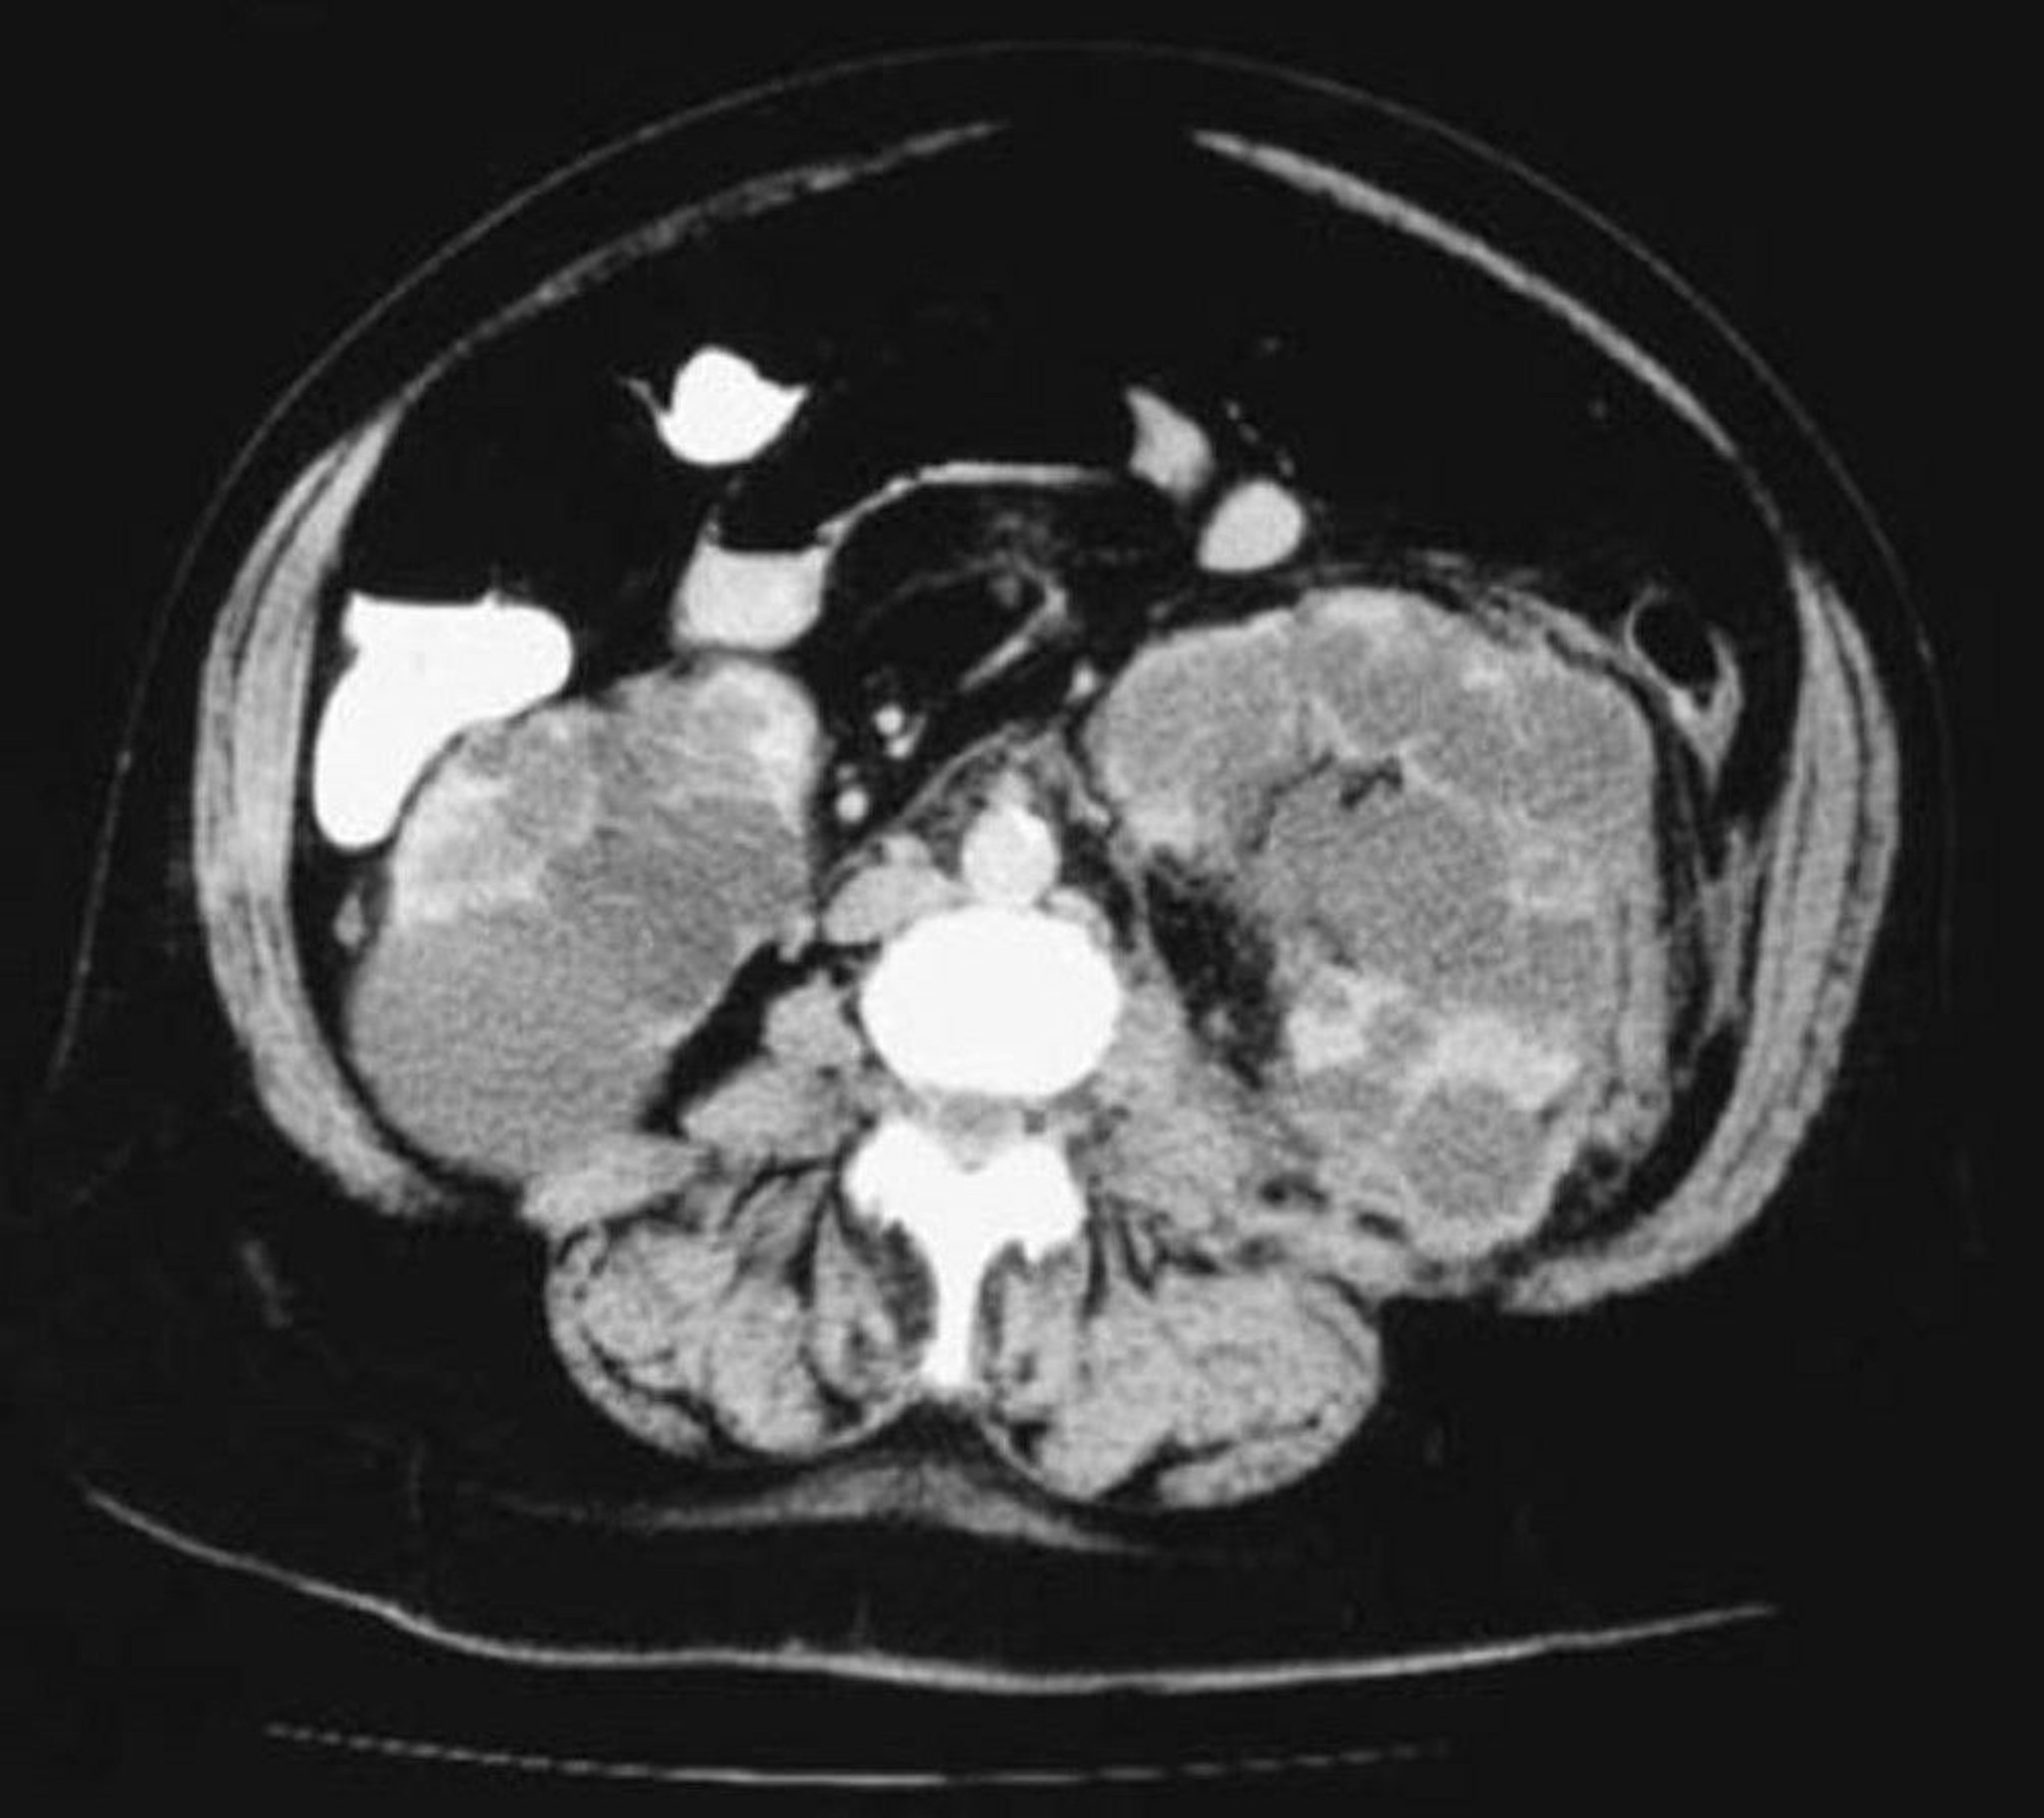

CT Axial View of Polycystic Kidneys

This CT scan of the kidneys shows numerous cysts varying in size. Little renal parenchyma is left.